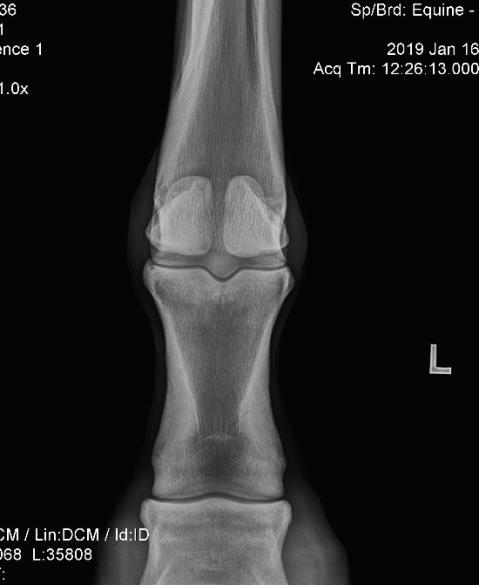

An example of a purchase examination where MRI was very helpful follows: The horse in question was a 12-year-old Grand Prix Dressage horse that had been successfully competing in FEI classes in Europe. Physical examination was unremarkable except for positive distal limb flexion tests in both forelimbs. There was no apparent lameness working on a lunge or under saddle. Radiographs indicated some varying bone densities in the subchondral bone of proximal P1in both forelimbs, suggestive of subchondral bone injury. An MRI unit was conveniently located nearby and an examination was recommended. A standing MRI examination of both fore fetlock regions was performed. Radiographic and MRI images are shown in Figure 16 and 17. Significant pathology was identified in the subchondral bone of proximal P1 in both forelimbs on radiography that appeared to be active on MRI (bone fluid or edema) (Figure 15). The horse was also discovered to have similar radiographic lesions in the RH fetlock.

The right fore fetlock appeared to have a more distinct area of intraosseous fluid signal and subchondral defects that presented a high risk for affecting future soundness (Figure 17). Th is information resulted in the buyer declining the purchase of the horse.

fetlock regions was performed Radiographic and MRI images are shown in Fig. 16 & 17. Significant pathology was identified in the subchondral bone of proximal P1 in both fore limbs on radiography that appeared to be active on MRI (bone fluid or edema) (Fig 15?). The horse was also discovered to have similar radiographic lesions in the RH fetlock.

The right fore fetlock appeared to have a more distinct area of intraosseous fluid signal and subchondral defects that presented a high risk for affecting future soundness (Fig 17) This information resulted in the buyer declining the purchase of the horse.

MRI provides a means by which to evaluate the current activity of bone lesions and accompanying soft tissue changes. While nuclear scintigraphy may give some idea of local bone activity or increased blood flow, MRI adds the benefit of providing information regarding osseous structure as well.